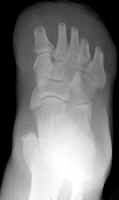

The images above demonstrate a transmetatarsal amputation through all five digits.

The bone edges are beveled and there is a generous soft tissue pad.